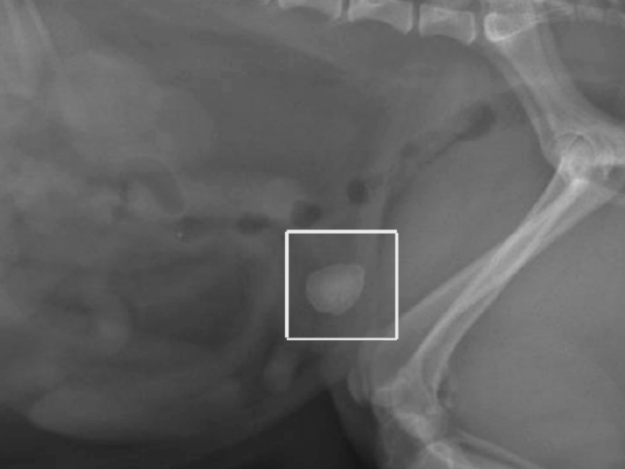

Cystotomy in Dogs and Cats